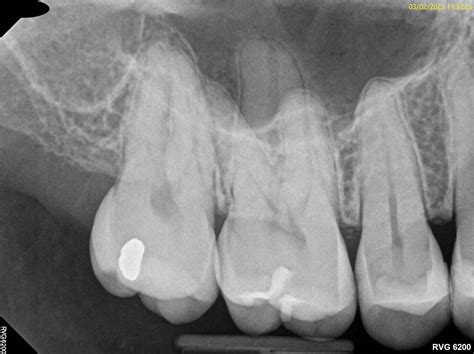

• Complex Anatomy: Sometimes, a tooth has extra canals that may have been missed during the initial treatment, allowing bacteria to remain and continue causing infection.

• Post-Procedure Infection: Rarely, bacteria can re-enter the treated area if the tooth seal is compromised.

You should not hesitate to schedule a follow-up appointment if your pain persists. Even if the root canal was performed perfectly, complications can arise. A dentist might need to perform an occlusal adjustment to file down a high spot on your crown or prescribe a course of antibiotics if there is a suspected persistent infection. In some cases, a retreatment or an apicoectomy (a minor surgical procedure to remove the tip of the root) may be necessary to resolve the Rct teeth pain for good.

• RCT Radiograph

• RCT Molar